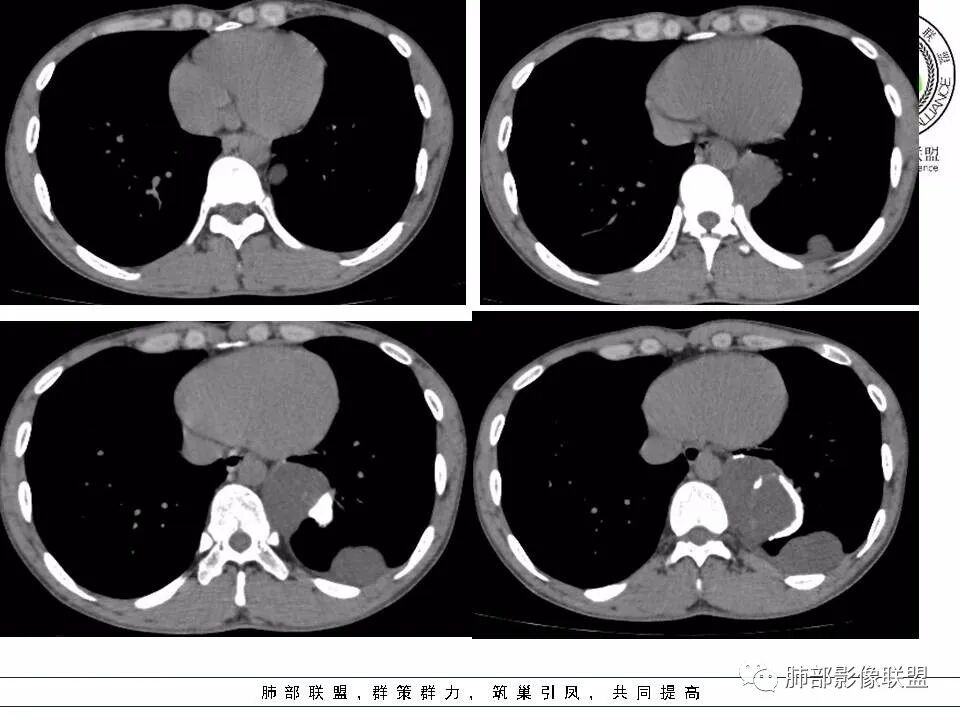

现在我们重新回顾性分析这个病例的影像特点:

1.含有少量脂肪密度成分,位于病灶中央区,应当是病灶内的一部分,或者说至少这部分不是被包绕卷入的。常见病灶内含有脂肪组织的肿瘤:多种脂肪瘤、脂肪肉瘤、畸胎瘤、其他肿瘤伴脂肪化生或分化。

2.病灶中间弧形稍高密度影,提示纤维组织可能,而且很有张力并呈分叶状,伴弧形钙化,提示这个倾向于病灶的包膜。

3.部位深在且四处侵入,含脂质较少或整体密度高于脂肪的脂肪类肿瘤应当想到脂肪肉瘤的可能性,因为它可以粘液样变。

但本例病灶边界清楚,有一定规模而相邻骨质未见异常,提示整体倾向良性或者恶性程度不高。

良性脂肪肿瘤有多种,脂肪瘤、纤维脂肪瘤、血管脂肪瘤、神经脂肪瘤、梭形细胞脂肪瘤、冬眠瘤等等……

4.冬眠瘤为含有棕色脂肪成分的脂肪瘤,又称为棕色脂肪瘤,因类似冬眠动物的冬眠腺而得名。良性,生长缓慢,好发年龄30-40岁,男性稍多。血管丰富有时会触及局部皮温相对高。

脂肪瘤临床触诊偏柔软较有特点,CT影像脂肪组织成分是最重要的依据之一。

本例无论是临床还是影像都可能怀疑到脂肪类肿瘤,但落实到冬眠瘤难度颇大。